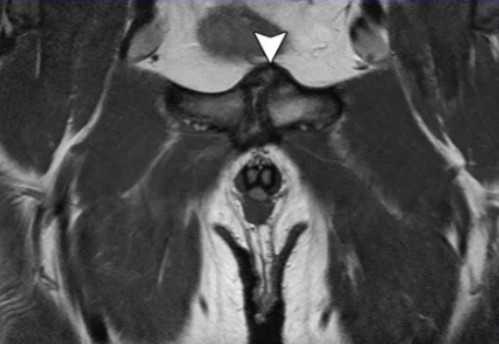

МРТ: симфизит, стрелка указывает на утолщение капсулы, неровность контуров

Сначала чаще используют компьютерную томографию. При сохранении необъяснимой боли в течение недели без видимых рентгенологических признаков показано выполнение магнитно-резонансного сканирования. Процедура важна для диагностики угрожающих состояний: аваскулярного некроза, злокачественного опухолевого процесса и пр. МР-томография демонстрирует максимально подробные изображения мягкотканных структур: мышц, связок, сухожилий, нервно-сосудистых пучков, что необходимо для определения правильного диагноза и дифференциации ряда суставных синдромов.